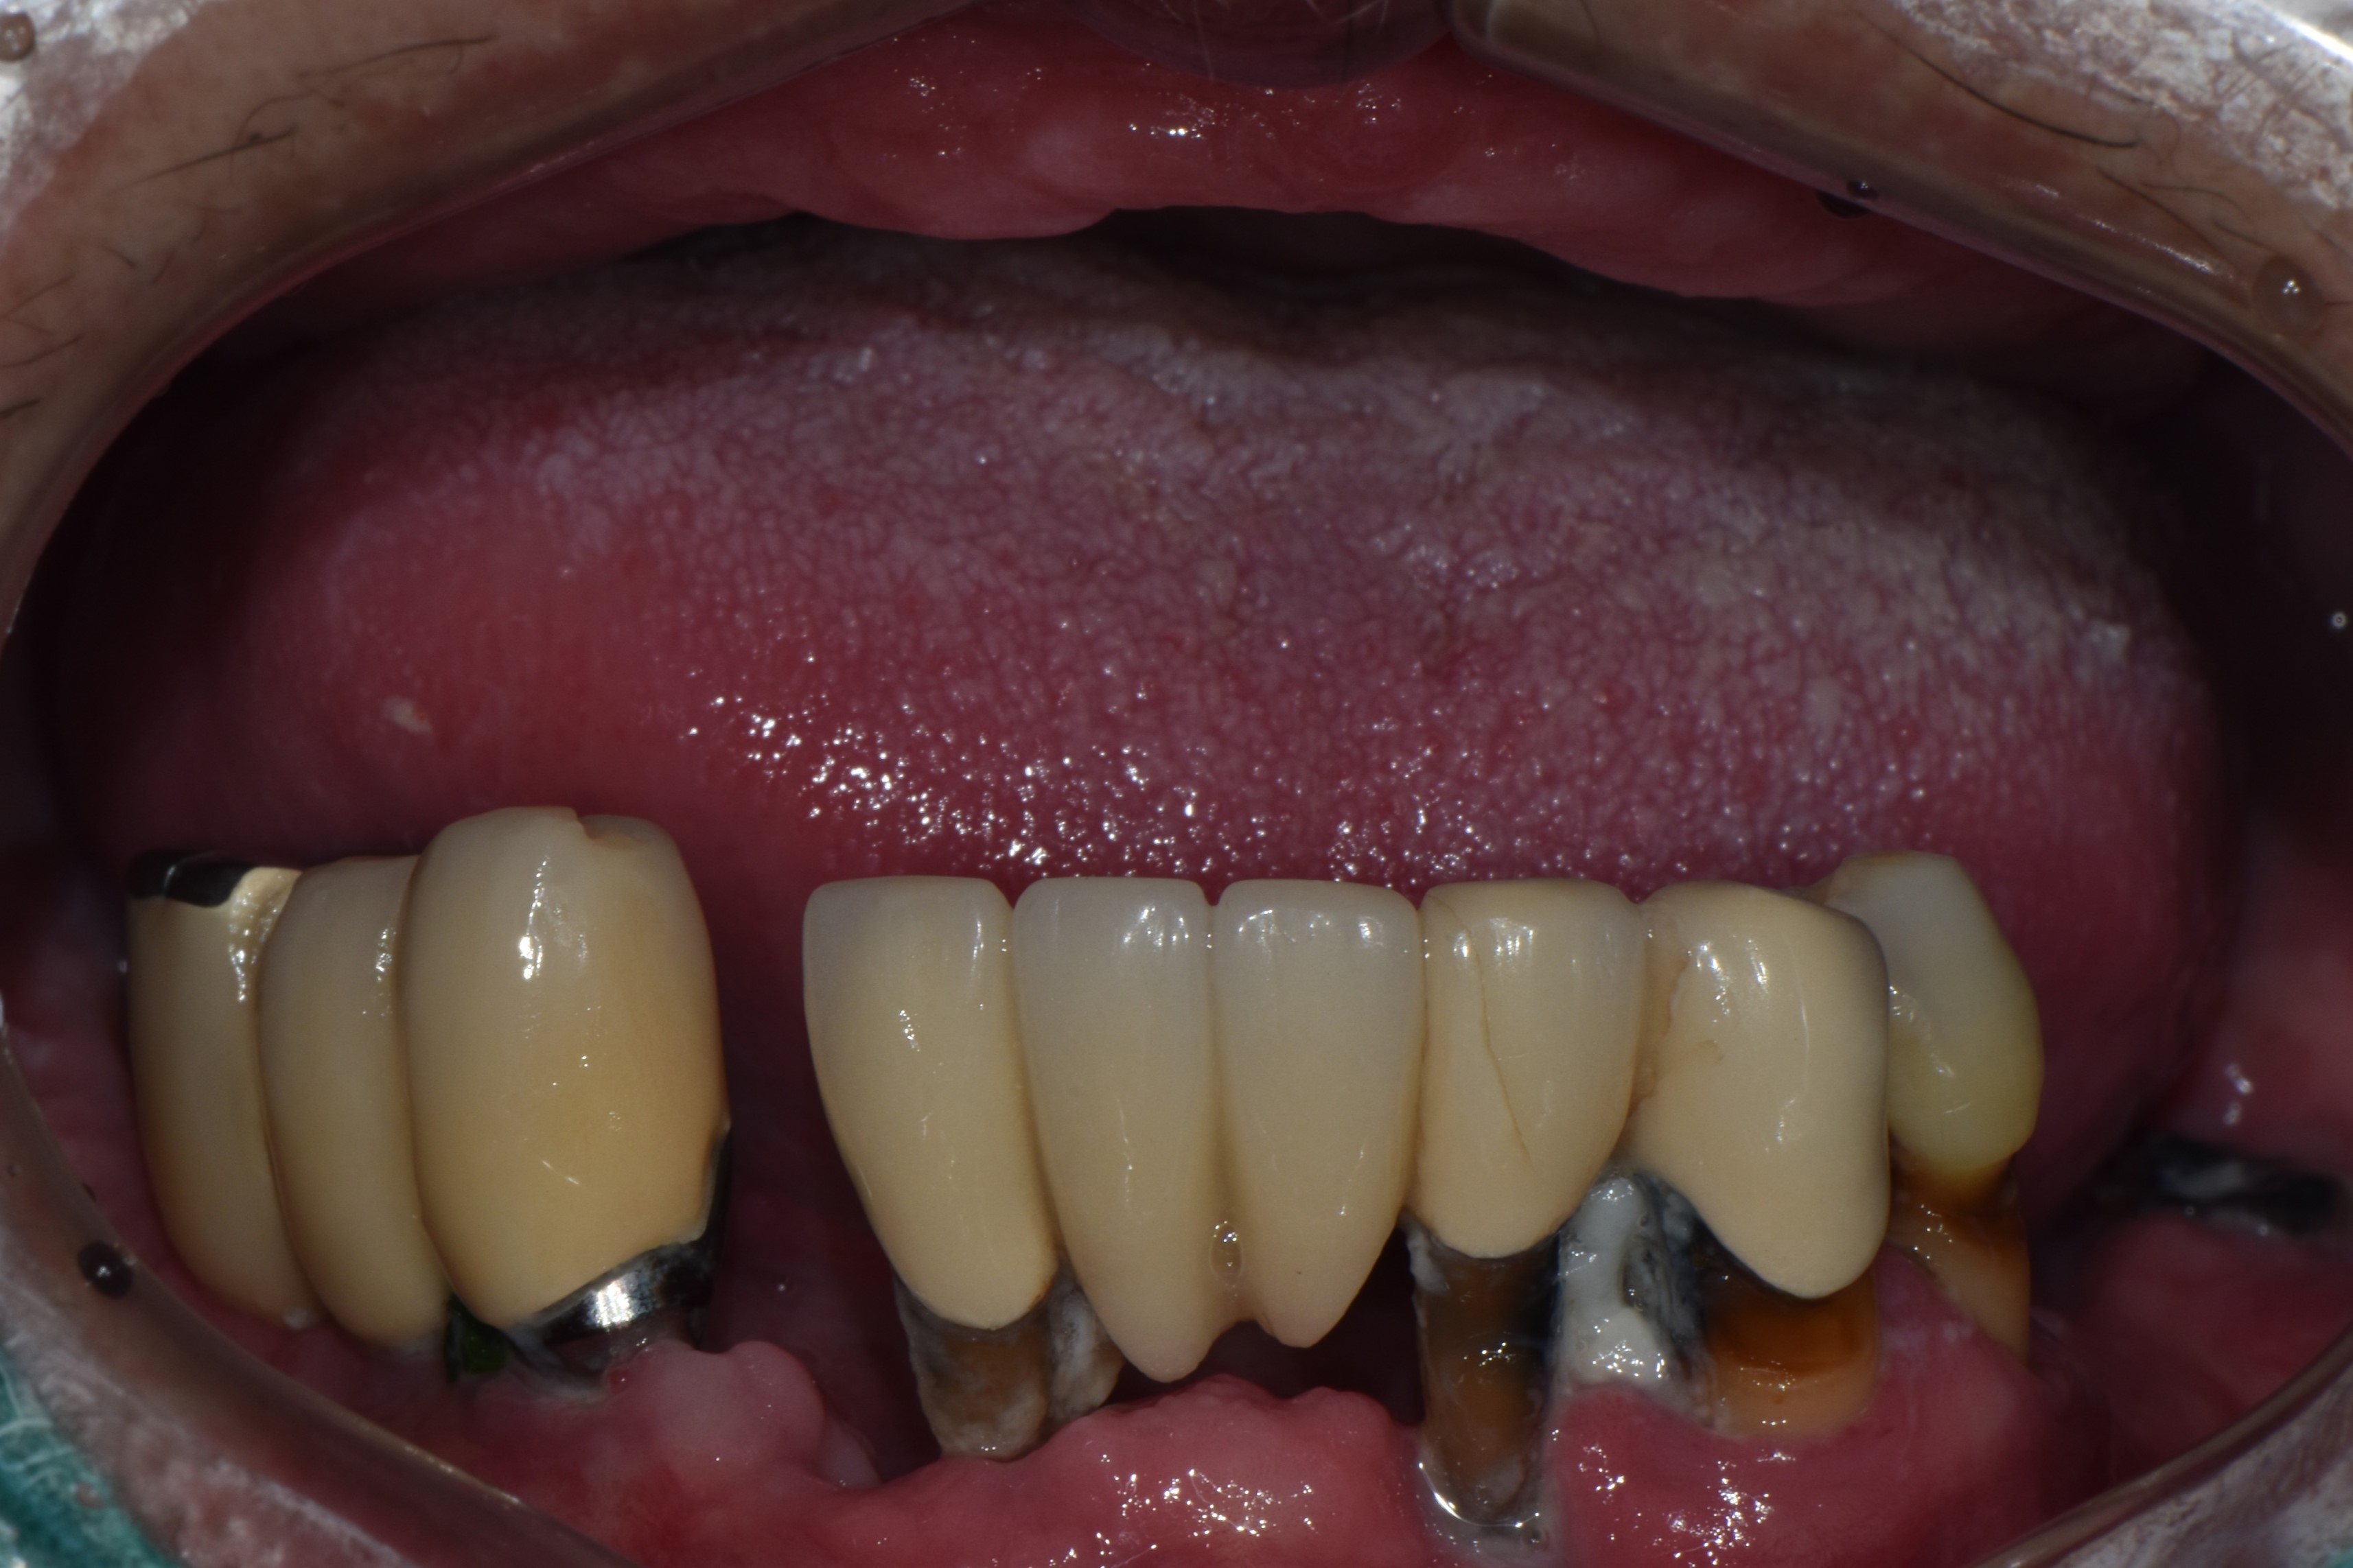

비강거상과 상악동거상을 동반한 전체임플란트 치료 증례 2026-02-20 hit.70 |

촬영일시: 2024.05.03

[ 치료기간: 2024년 05월 03일 ~2025년 03월 14일 ] ※ 365서울앞선치과의원의 모든 컬럼은 각 진료과 의료진이 직접 작성합니다. 365서울앞선치과의원 임상 케이스 게시물은 환자분께 의학적으로 정확하고 상세한 정보를 드리기 위해 각 진료과 의료진이 직접 작성하며, 모든 증례 사진은 본원 의료진이 직접 시술한 증례를 촬영한 것으로, 의료법 제23조, 제56조에 의거하며 환자분의 동의를 얻어 포스팅에 사용하였습니다. 또한 해당 케이스는 본 환자분의 치료 결과이며, 환자 상태에 따라 치료의 결과는 달라질 수 있습니다. |